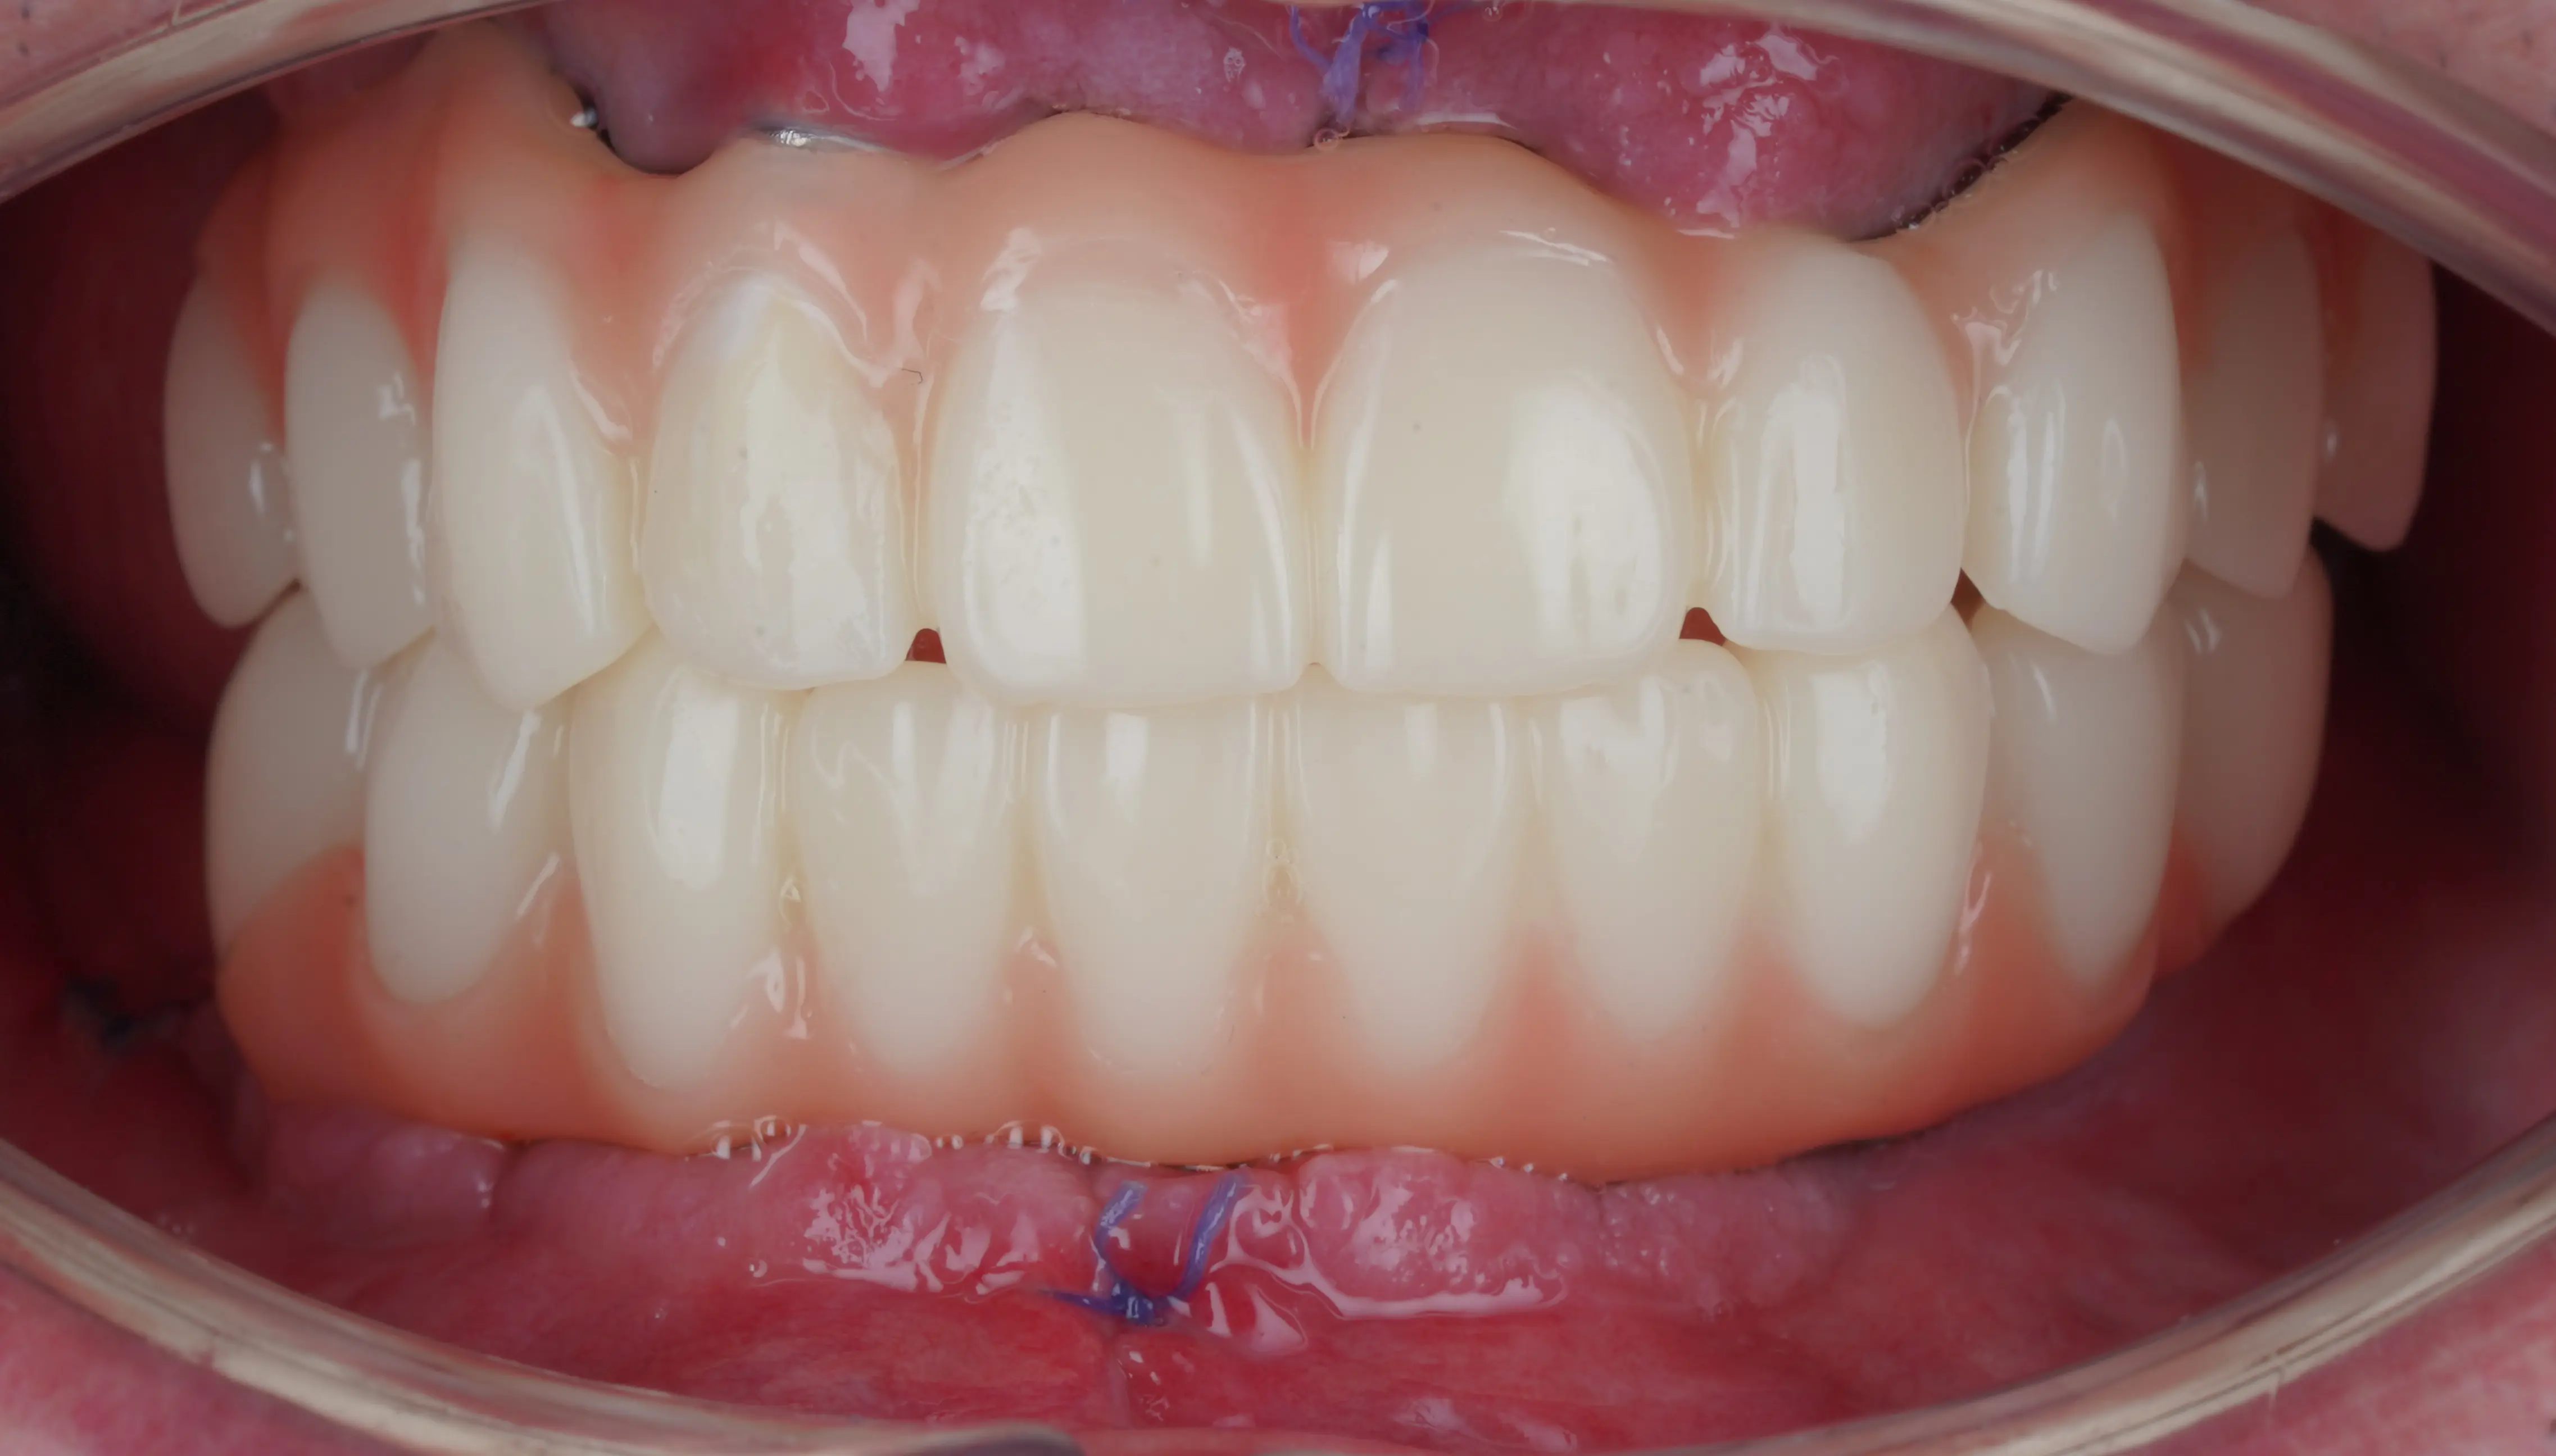

Proteză montată imediat după procedură

Aceeași proteză, după 6 luni

(se poate observa gingia cum s-a retras)